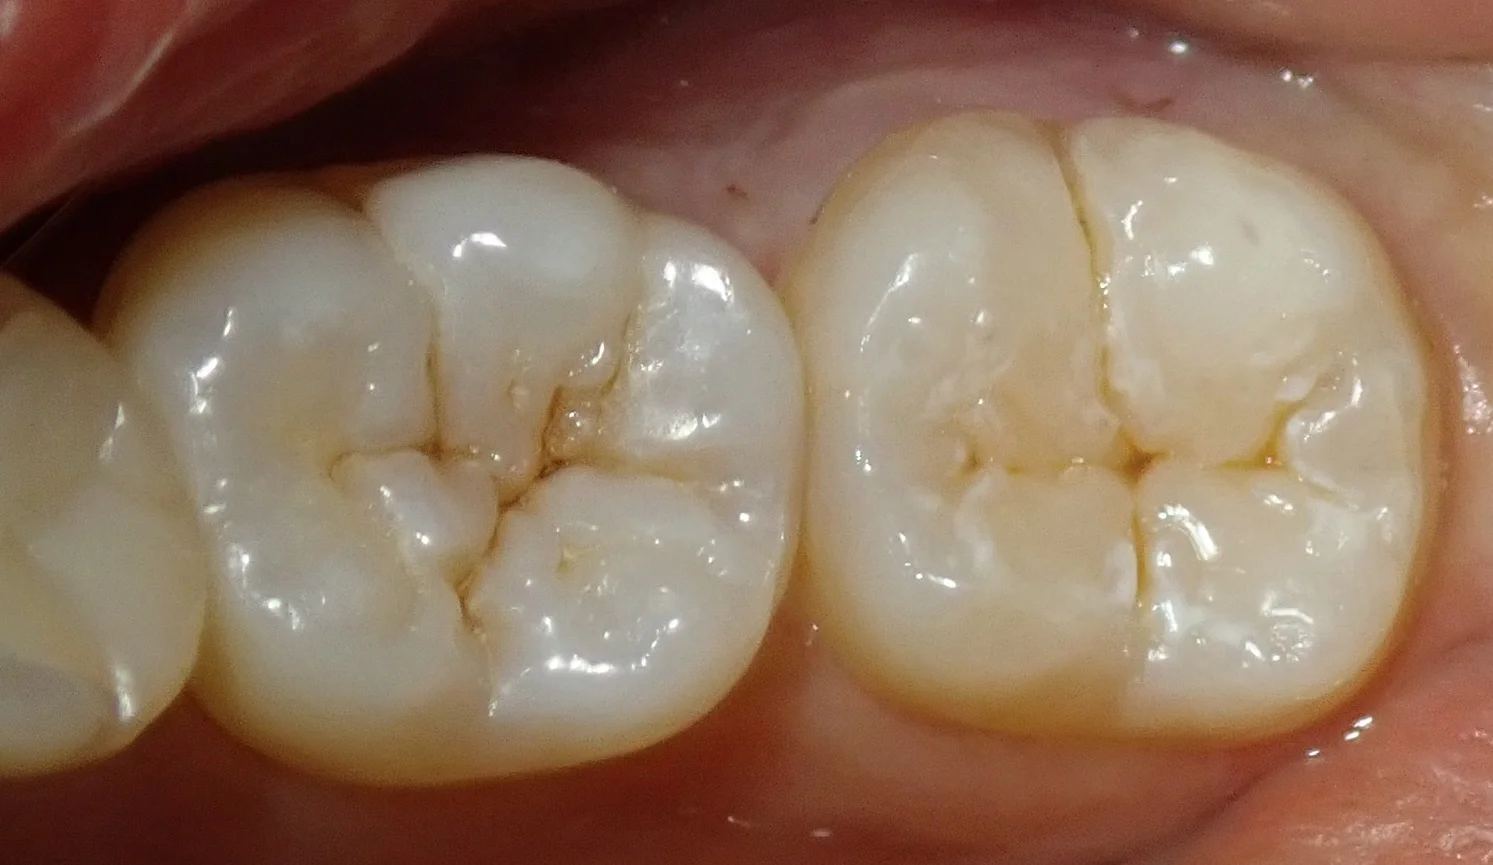

そして、ダイレクトボンディングを行い、噛み合わせの調整を終えたのがこちら。

溝の色は左側の天然の歯になるべく近いように色を作って付けました。

歯の色が乾燥しているため、白っぽくなっていますが、水分が戻ってくるとこの色の違いは消えて綺麗に馴染んできます。

このまましっかりと長持ちしてくれれば良いなと思いますヽ(゚∀゚)ノ パッ☆